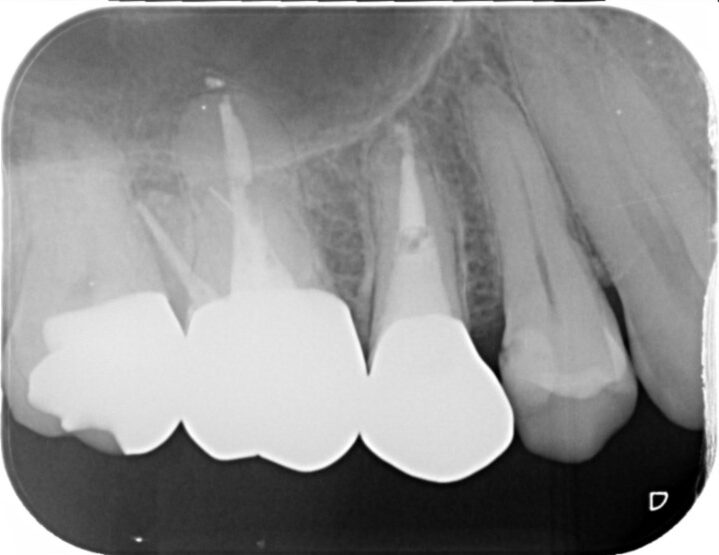

Case

60代女性

ひびが入っている根っこがあることがわかります。

ひびが入っていた根っこ以外を利用してできるだけ抜歯を避けました。

見た目も違和感なく被せ物をかぶせることができました。

治療部位 | 右下6番 |

費用 | 約100000円 |

治療期間 | 9ヶ月 |

他院で作成された被せ物をやり替えた際にお痛みがあり、再度治療を始めたがこれ以上の治療はできないと言われてしまい治療中断。

悩まれた末に当院にご来院くださりお話をお聞きしました。

1つの根っこにひびが入っていることなどがわかりましたが抜歯ではなく、できるだけ歯を残存させることを目的とした治療計画を立てて根っこの治療を開始しました。